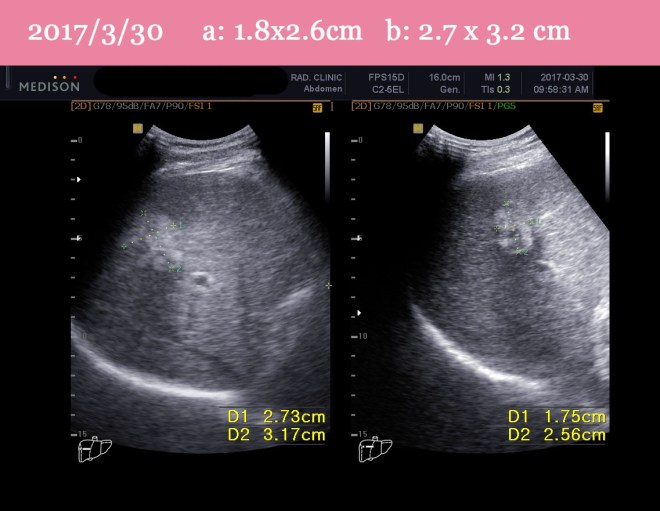

| 2017/3/9 | 강남 영상의학과 초음파 검사. S8. 2.1x 3.0cm S5 2.7x 3.0cm(WXD) | 초음파 검사 |

| 2017/3/31 | 강남 영상의학과 초음파 검사 com with 2017/3/9

2.1×3.0cm(WxD, S8) and 2.7×3.0cm(WxD,S5) -> 1.8 x 2.6cm(more regressed) and 2.7 x 3.2cm(no interval change) |

초음파 검사 |

| 2017/5/18 | ABDOMINAL SONOGRAM : Comparison with2017-03-30

1. Known HCC, post-TACE state 2. Previously noted an irregular hyperechoic lesion in the right hepatic lobe is seen again with more regression; (2.7 x 3.2cm ->1.8 x 2.8cm). Previously noted another hypoechoic lesion is not identified in this study. |

초음파 검사

두개 중에 하나는 없어지고 작은 것은 줄어들음 |

- 치료 시작 전 (2017/3/9) ABDOMINAL SONOGRAM :

- Known HCC, post-TACE state

- 2.1×3.0cm(WxD, S8) and 2.7×3.0cm(WxD,S5) sized irregular hyperechoic lesions in the right hepatic lobe, compatible with HCC

2. 치료 20일 뒤 (2017/3/31)

한방약물 단독 치료 20일 후 – 식이요법 소음인 식이요법으로 – 짜고 맵게 식사지도

강남 영상의학과 초음파 검사 com with 2017/3/9

2.1×3.0cm(WxD, S8) and 2.7×3.0cm(WxD,S5) -> 1.8 x 2.6cm(more regressed) and 2.7 x 3.2cm(no interval change)

3. 치료 두달 뒤 (2017/5/18) ABDOMINAL SONOGRAM : Comparison with2017-03-30

- previously noted an irregular hyperechoic lesion in the right hepatic lobe is seen again with more regression; (2.7 x 3.2cm ->1.8 x 2.8cm).

- Previously noted another hypoechoic lesion is not identified in this study.